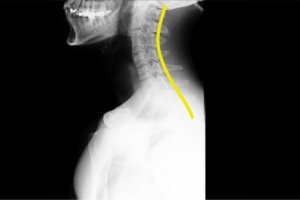

整体や整骨院では「骨格の歪み調整」「関節の動きの改善」「筋肉バランスの是正」など、目に見えない部分を重点的にケア。施術中だけでなく、日常生活の体の使い方のクセ、歩き方や立つ姿勢、椅子の座り方まで丁寧に見直し、長期的に症状が出にくい体づくりを目指しています。